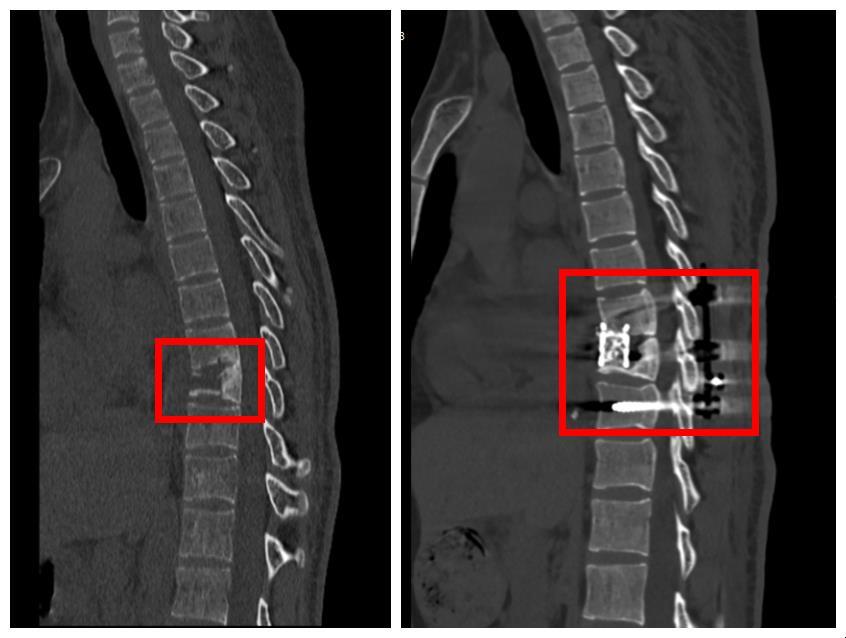

治疗前后的对比

通过单孔胸腔镜清除肺上的脓胸病灶,在武汉市肺科医院已很成熟,但医生还需进行胸椎植骨融合及钛钉内固定,这一般需要开胸才能完成。为了减少手术创伤,该院外科专家思索一次手术解决两个问题的可行性。

术中,刘小玉和徐风首先通过内固定方式,使用钛钉牢牢固定住了遭受病菌侵蚀的胸椎,然后在小刘右侧胸腔开了一个4厘米左右的小孔,清除了脓胸病灶。之后,他们通过胸腔镜技术避开了不断膨胀又收缩的肺,锁定并清理胸椎上的病灶,为患者进行了胸椎植骨融合术。